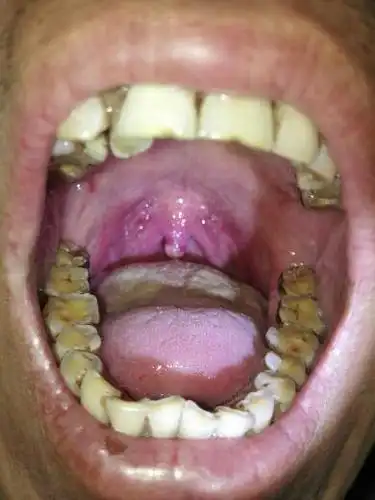

求救 求救求救 懂的医师 专家 麻烦耽误几分钟给我看一下 开始悬雍垂